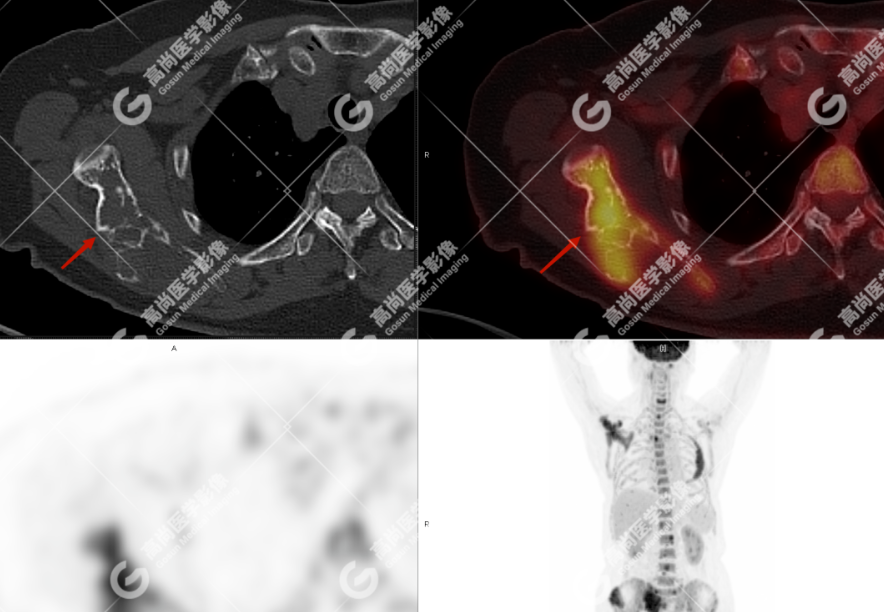

颅骨、寰椎前弓左侧份、第 6 颈椎、双侧肩胛骨(右侧为著)、左侧第 4 肋骨、第 1 胸椎、第 4 胸椎、第 2 腰椎及附件、第 4 腰椎及附件、骶骨、右侧髂骨、左侧坐骨结节、左侧股骨颈、双侧股骨小转子等均不同程度骨质吸收、破坏,其中右侧肩胛骨、左侧第 4 肋骨及骶骨右侧份软组织肿块影形成,上述病变均考虑恶性肿瘤(血液系统来源,多发骨髓瘤可能性大),建议右侧髂骨翼穿刺活检明确。

(4)PET-CT 影像表现:在溶骨性破坏区出现相重叠的 18F- FDG 高代谢区;通常呈弥漫性高代谢区。